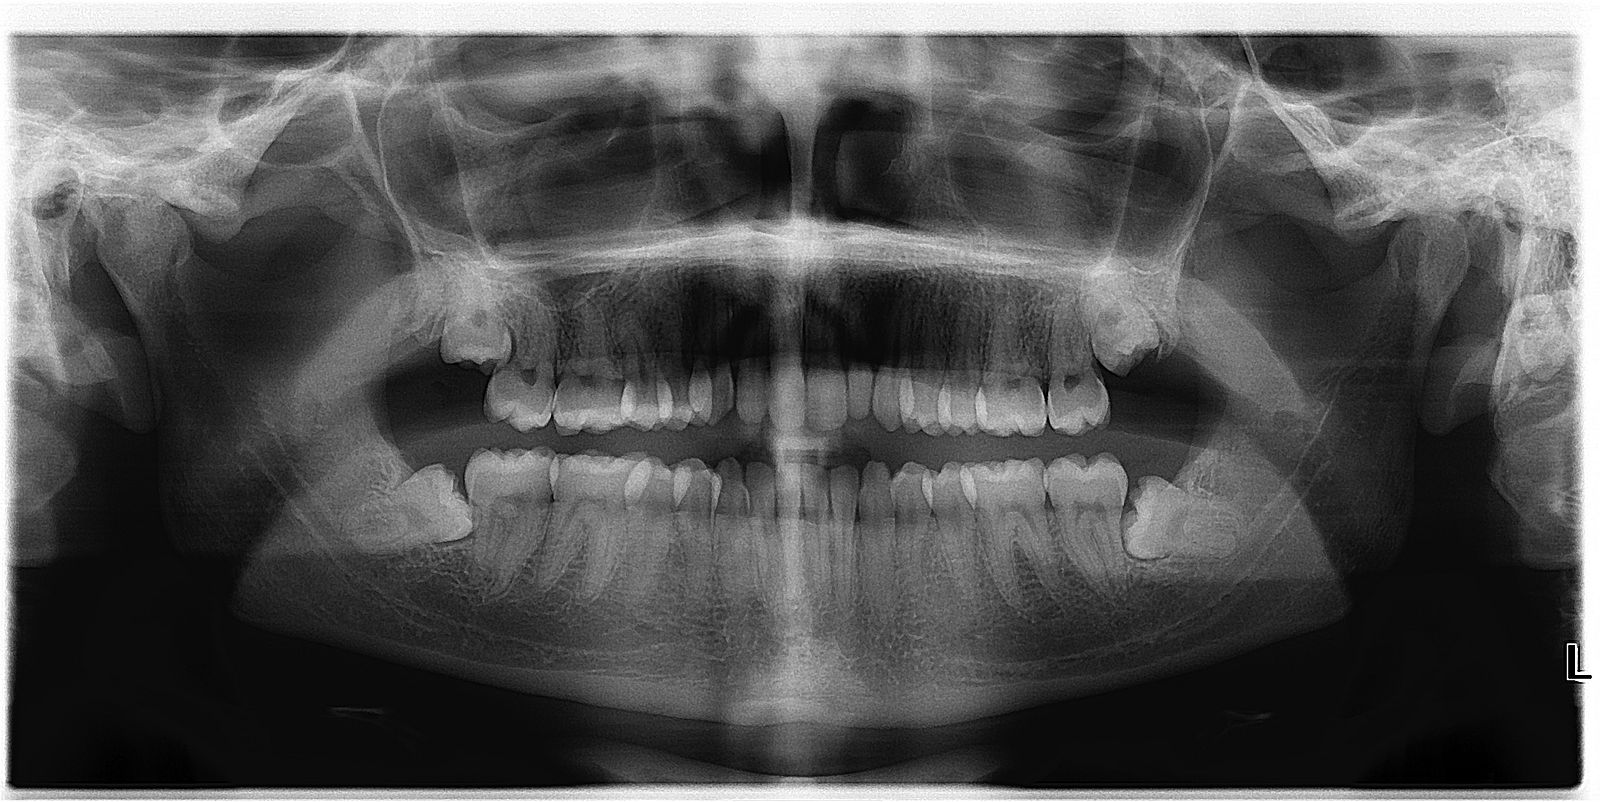

牙医总爱劝我们拔智齿,但其后果却令很多人担心:“拔掉智齿有什么后果?会影响味觉吗?”据近日发表在英国《化学感官》杂志上的论文,美国宾夕法尼亚大学牙科医学院的研究人员发现,拔智齿可以改善味觉,而且该影响会持续很长时间。

1600px-Asymptomatic_disease_free_impacted_wisdom_teeth.jpg

资料图